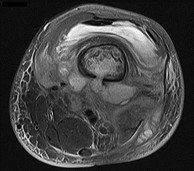

Figures 6a through 6d are the radiographs and T1-weighted sagittal and fat-saturated axial MR images of an otherwise healthy 56-year-old man who has anterior knee pain and intermittent swelling after sustaining a noncontact twisting injury. Low-power and high-power hematoxylin and eosin stained histologic specimens are shown in Figures 6e and 6f. Based on the history, radiographs, CT scan, MR imaging, and histologic findings, what is the most likely diagnosis?

The lesion in the posterior intercondylar knee notch is a benign synovial hemangioma. Intralesional calcifications, classically associated with hemangiomas, are frequently not identified on plain radiographs. The MR imaging reveals a hypervascular lesion with multiple filling defects, with hyperintensity on T2-weighted images and low-to-intermediate signal intensity on T1-weighted images. Histologically, vascular lakes within fine capillaries with a synovium on the surface of the lesion are characteristic of this condition. Many patients with synovial hemangioma have pain, swelling, stiffness, or mechanical symptoms. The correlation of symptoms with the hemangioma for this patient is unclear because there was recent trauma and a concurrent meniscus tear. Simultaneous treatment of both potential sources of pain is typically recommended. As with PVNS, the disease can be localized or diffuse. Surgical excision, either open or arthroscopic, is the recommended treatment. PVNS is the most common intra-articular tumor, but hypointensity in either the diffuse or localized type is characteristic in both T1- and T2-weighted images. Synovial sarcoma, although often found close to a joint, is not characteristically found within a joint.